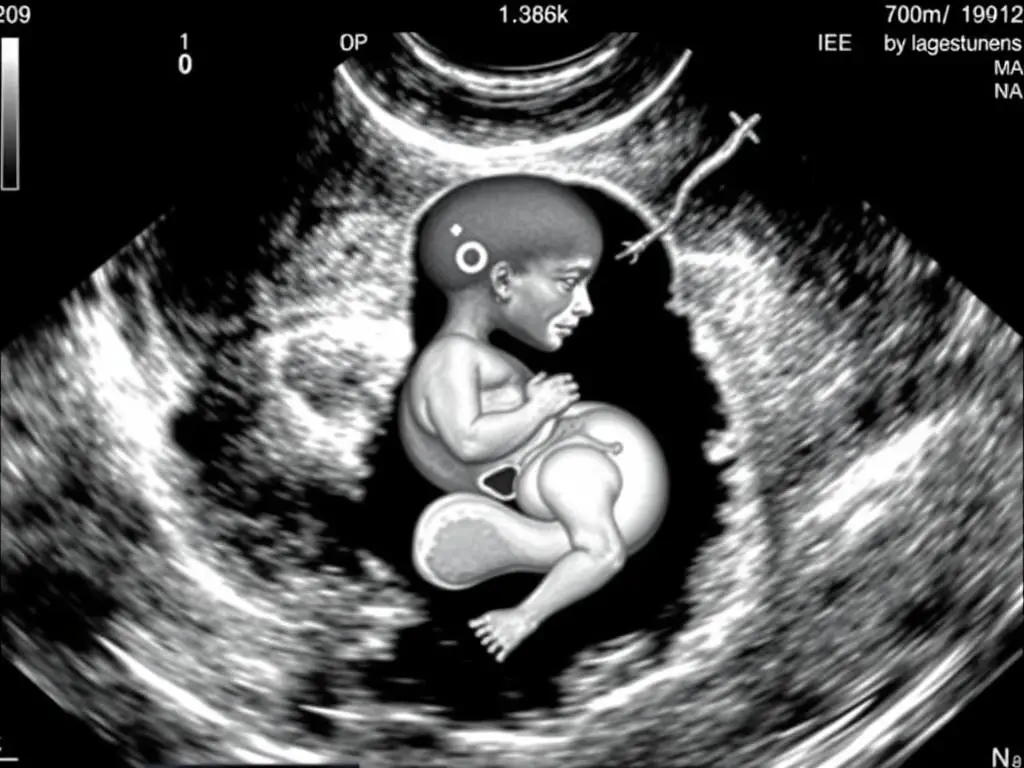

Trójwymiarowe USG płodu w 34. tygodniu ciąży pokazujące rysy twarzy

Ósmy miesiąc ciąży to czas, gdy:

- Płód nadal intensywnie przybiera na wadze

- Płuca płodu dojrzewają, przygotowując się do oddychania powietrzem

- Układ odpornościowy rozwija się, a płód otrzymuje przeciwciała od matki

- Przestrzeń w macicy staje się ograniczona, co może zmniejszyć intensywność ruchów płodu

- Pod koniec 35. tygodnia płód ma około 45 cm długości i waży około 2500 g

- Dziecko urodzone w tym okresie ma duże szanse na przeżycie bez poważnych komplikacji [13]